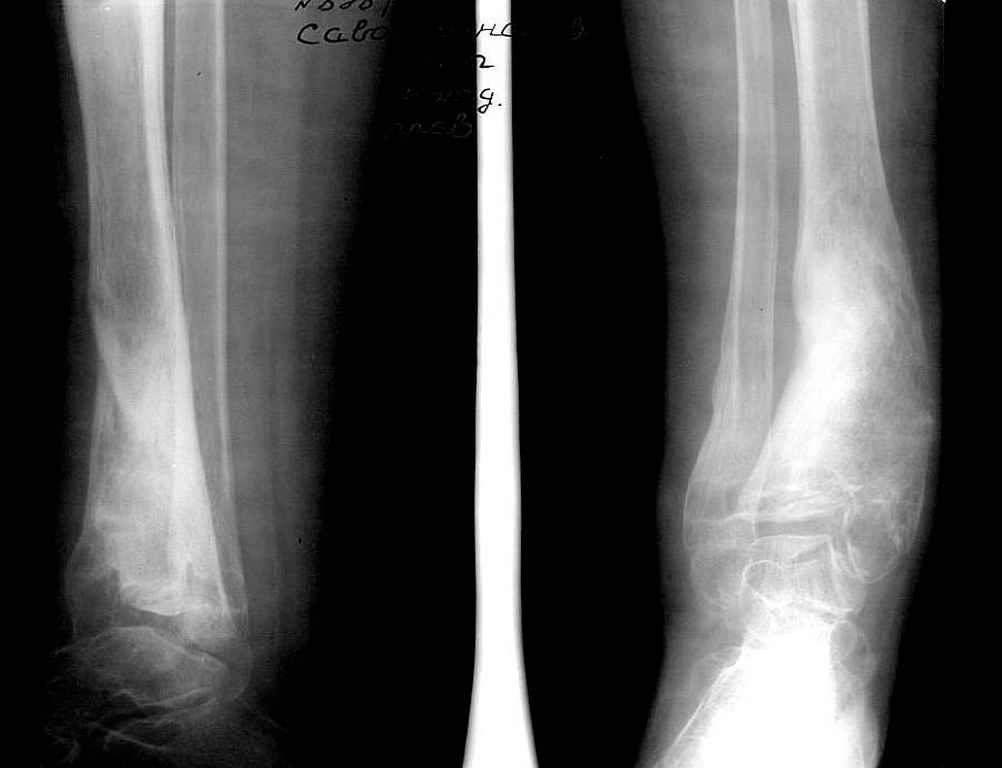

Девушка 17 лет: боли в голеностопном суставе,ограничение движений в суставе,укорочение голени,хромота

Из анамнеза в раннем детском возрасте перенесла гематогенный остеомиелит дистального отдела большеберцовой кости - зона роста частично закрылась сформировалась варусная деформация голеностопного сустава + укорочение костей голени на 6 см Произведена корригирующе-удлиняющая остеотомия сначала большеберцовой,затем малоберцовой костей, устранена деформация, ликвидировано укорочение. С возрастом наросло укорочение до 3 см,клинически умеренная вальгусная деформация голеностопного сустава. Объём движений в суставе в пределах 15 град. Отмечает переодически болевой синдром, после осевой перегрузки,пользуется обувью с компенсацией, ортезом на голеностопный сустав

Вопрос: есть ли показания для оперативного лечения: артропластика? артродез? голеностопного сустава. Какие мысли,коллеги?